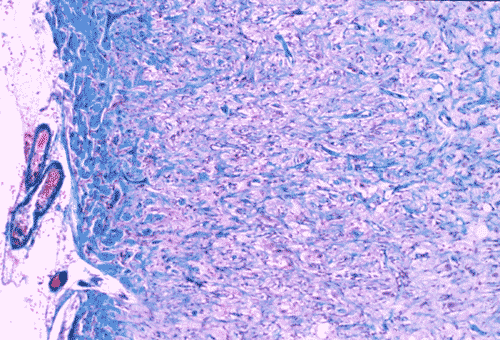

Histopathology: On histologic examination, the cortex lesion (C-L in Panel A) appear fibrous and vascular. It is well demarcated from the white matter (W in Panel A). The cortical lesion respects the grey-white junction and the interface is smooth. These features are better appreciated on Masson's trichrome stain. While one side of the gyrus is replaced by the lesion (C-L in Panel E), normal cortex is present on the other side of the gyrus (C-N in Panel E). White matter (W in Panel E) and the normal cortex (C-N in Panel E) carry a pink hue on Masson's trichrome.he fibrous lesion (C-L in Panel E) does not carry much of this pink hue.  The lesion essentially follow the shape of the gyrus with some cortical thickening (Panel F). On higher magnification, the cortical lesion is highly vascular (Panel B, C, and G). In between the fibrous vascular component, there are entrapped islands of cortical tissue (Panel D, H, and I ). There is a general lack of pleomorphism and mitotic activities in the lesion.

Histologically, the salient feature is a disorganized lesion featured by perivascular meningothelial cells intermingled with a fine, rich vascular network. Although each lesion is unique, increased cortical vascularity and perivascular cellular proliferation are constant findings. Irregularly branched blood vessels extending into the gray matter from the meningeal surface are surrounded by a concentric arrangement of proliferating spindle-formed cells .The overall structure can occur as nodules, whorls, or bands. Islands of cortical tissue with gliosis are often trapped within the lesion. The ratio between meningothelial component and vascular component varies substantially. There are lesions predominantly composed of vascular component or meningothelial component 3. A schwannian component can also occur. There are also cortical meningovascular fibroblastic proliferation and leptomeningeal calcifications that range from faint psammomatous calcification to dense osteoid. Residual neurons entrapped within the lesion may contain neurofibrillary tangles with ultrastructural and immunostaining properties identical to those seen in Alzheimer's disease but there is no deposition of amyloid Ab.